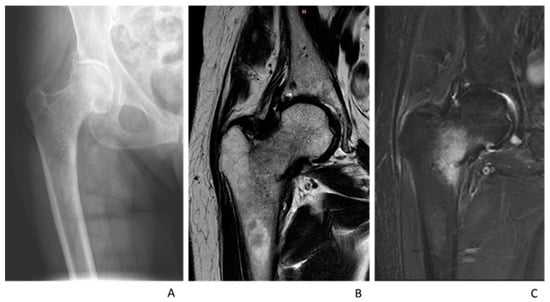

:1. Introduction

2. Materials and Methods

2.2. Radiography and Radiological Indices

2.3. MRI